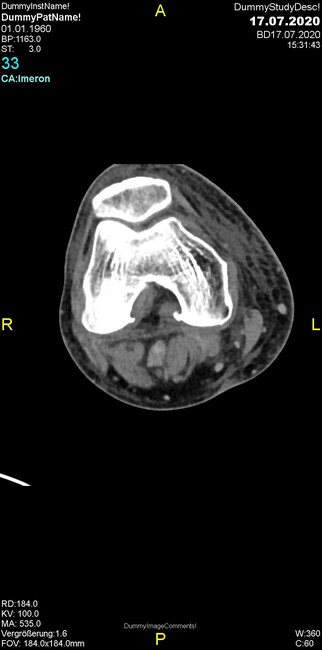

Was fällt in der CT im Knochenfenster auf?

- Mediale Gelenkspaltverschmälerung

- Dezente Erosion der fibulären Kortikalis

- Frakturspalt der lateralen Tibiametaphyse

- Weichgewebskalzifikationen lateral angrenzend an den Gelenkspalt

- Osteolyse der Tibiametaphyse unter Beteiligung der Kortikalis

Was kommt differentialdiagnostisch in Frage?

- Kompartmentsyndrom

- Osteomyelitis mit Weichgewebsanteil

- Metastase mit pathologischer Fraktur

- Rheumatoide Athritis

- Posttraumatische Verletzung